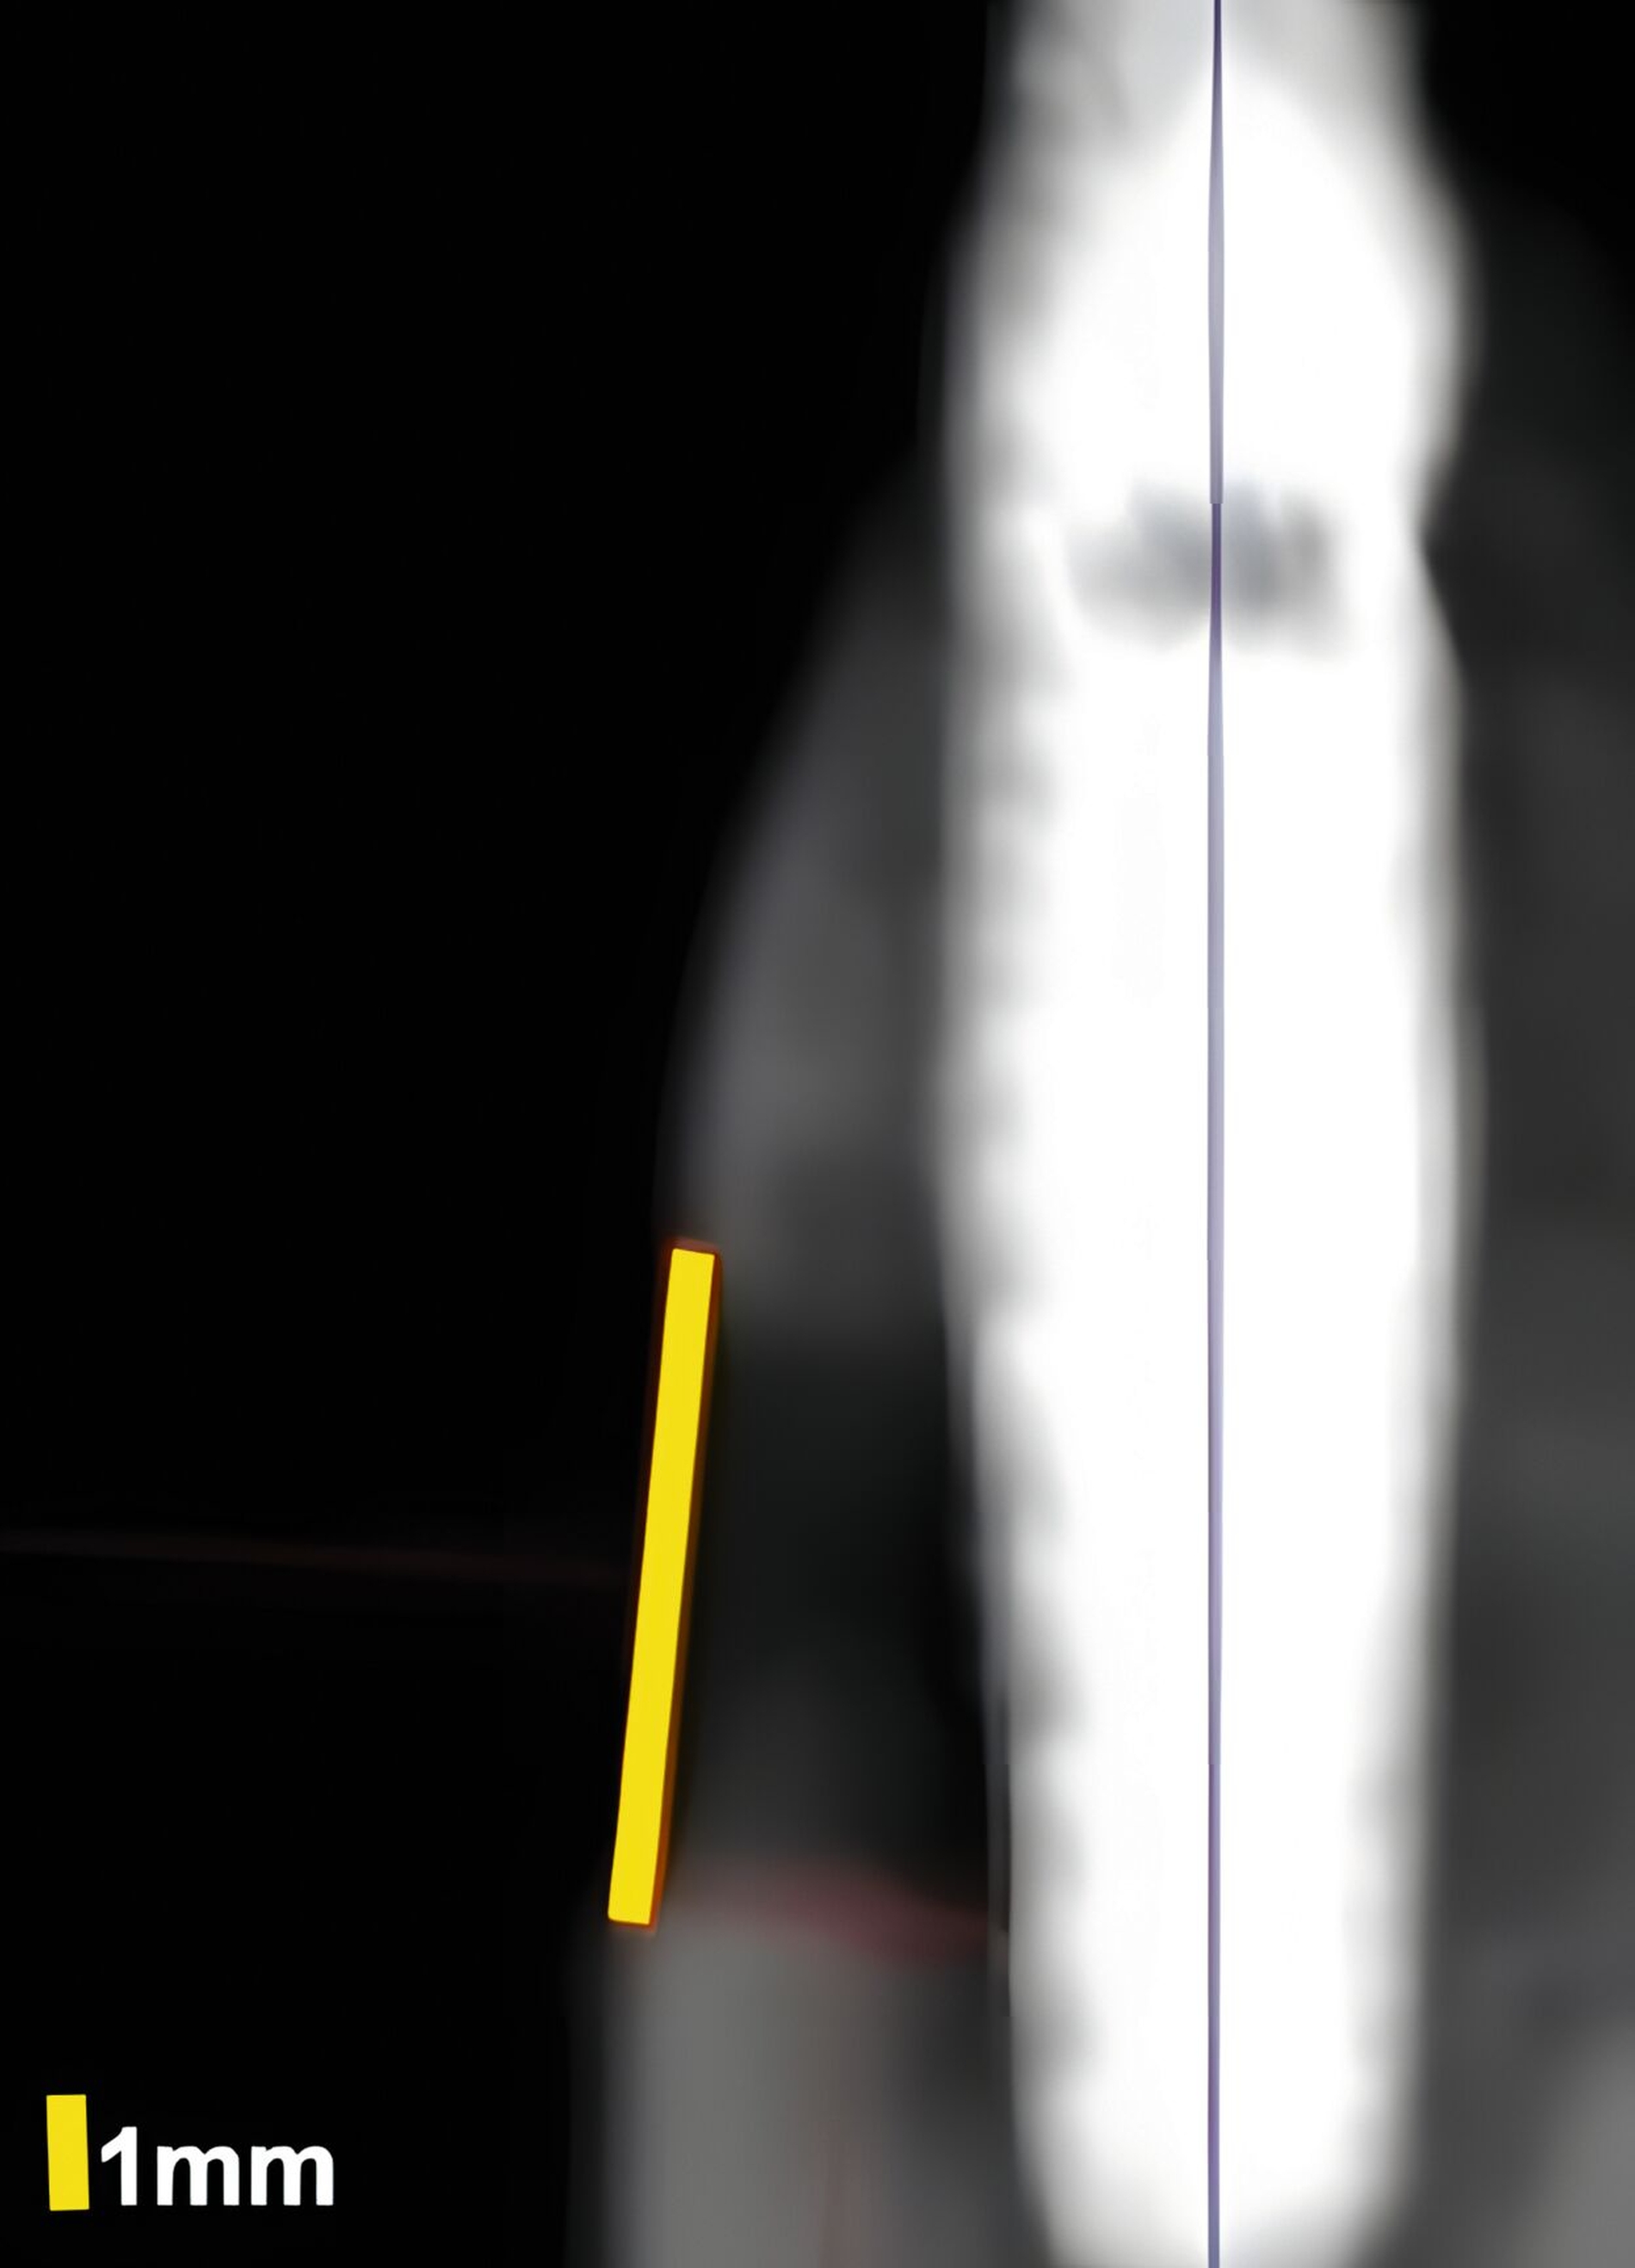

Dies konnte in einer ebenfalls eigenen humanen Kadaverstudie bestätigt werden [Bykhovsky et al., 2024]. Dabei wurden an Implantaten standardisiert Fenestrationen (n = 7), Dehiszenzen (n = 14) und dreiwandige Knochendefekte (n = 6) präpariert (Abbildungen 6 bis 8). Die Defekte wurden mit US- und DVT-Aufnahmen untersucht und die Messungen mit den direkten Messungen verglichen. Die US-Messungen zeigten eine starke Korrelation mit den direkten und den DVT-Messungen. Die sonografische Messgenauigkeit war bei Dehiszenzen am höchsten, gefolgt von Fenestrationen und dreiwandigen Knochendefekten.

In einer aktuellen klinischen Fallserien-Studie wurden impaktierte Oberkiefer-Eckzähne mittels DVT und US-Scanner (30-MHz -Sonde, L-30-8, ZS3, Mindray, Mountain View CA, USA) untersucht [Yatabe et al., 2024]. Der US zeigte sich effektiv in der Lokalisierung der Zähne und in der Beurteilung von Weichgewebsdicke und Gefäßstrukturen, was die chirurgische Planung erleichtert.